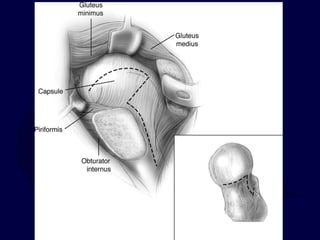

Sciatic Nerve

Composed from roots of L4 to S3.

Passes posterior to posterior wall of acetabulum.

Generally passes inferior to piriformis muscle, but

occasionally the piriformis will split the peroneal

and tibial components